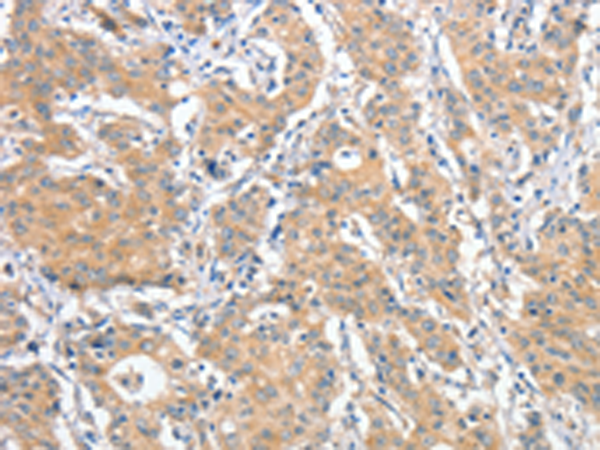

分类: 科研抗体货号: P07833别名: CALS-7; MDS015; ALS2CR1应用: WB,IHC反应种属: Human, Mouse, Rat